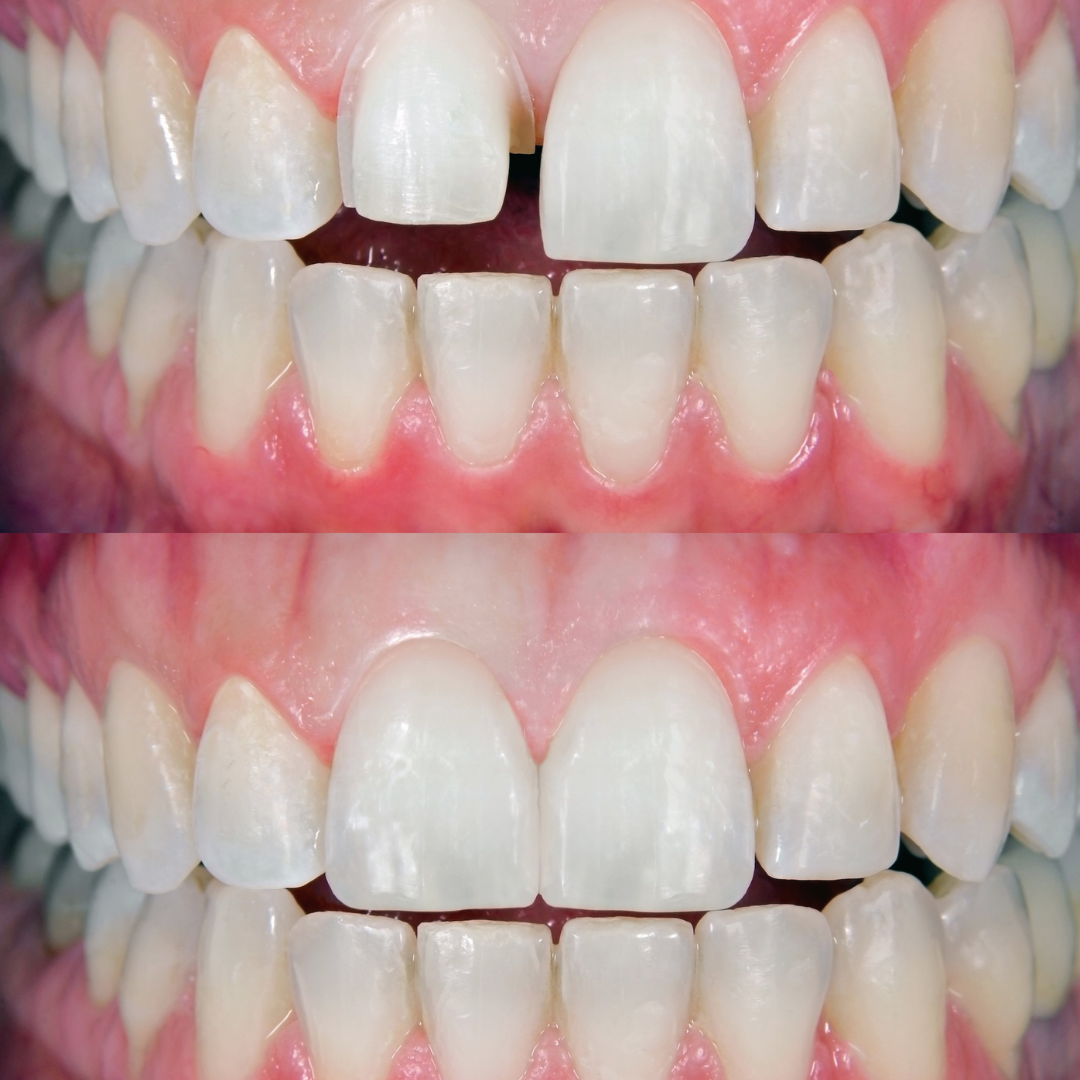

বন্ডিং ট্রিটমেন্ট একটি দাঁতের পুনর্গঠন প্রক্রিয়া!

যা বিশেষ টুথ-কালার রেজিন ব্যবহার করে দাঁতের ফাটল, ক্ষয়, চিপ বা রঙ পরিবর্তন মেরামত করে। এটি দাঁতের ফাঁক বন্ধ করতেও সাহায্য করে।

Restorative dental treatments aim to restore damaged or decayed teeth to their natural function and appearance.

Cosmetic dental treatments aim to improve the appearance of teeth and give patients a more attractive smile.